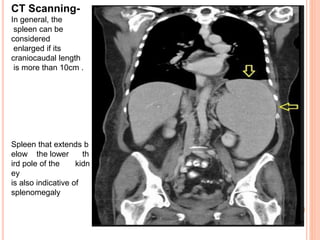

CT Scanning-

In general, the

spleen can be

considered

enlarged if its

craniocaudal length

is more than 10cm .

Spleen that extends b

elow the lower th

ird pole of the kidn

ey

is also indicative of

splenomegaly